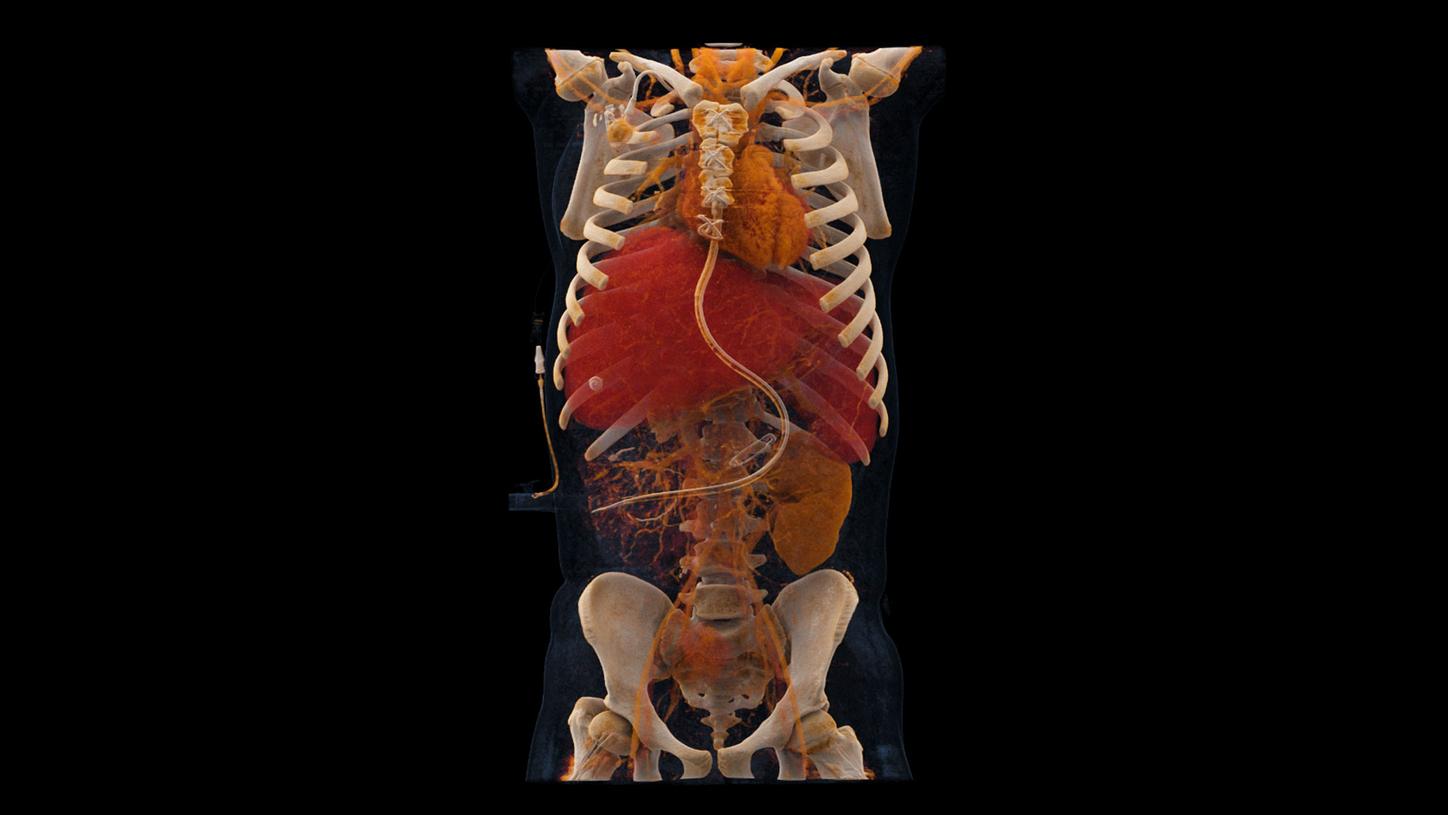

In 2021, NAEOTOM Alpha® with Quantum Technology was the first photon-counting CT in clinical use. And now, the next generation has arrived: NAEOTOM® Alpha.Peak debuts with the proven technology of the original as the pinnacle of the NAEOTOM Alpha class. Explore the evolution.

NAEOTOM Alpha with Quantum Technology, the world's first photon-counting CT, marked the beginning of the photon-counting CT era. Its never-seen before technology is designed to guide therapeutic and clinical decision-making for more patients.

At the heart of NAEOTOM Alpha® is a radically new photon-counting detector. The QuantaMax detector directly converts X-rays into an electrical signal, which is then used to create an image. The energy of each X-ray is measured, so spectral information is available for every scan, and the images are contrast-rich with high spatial resolution at the same dose. Combining the high spatial resolution of the QuantaMax photon-counting detector with our Dual Source temporal resolution enables the visualization of fine details for increased diagnostic confidence.